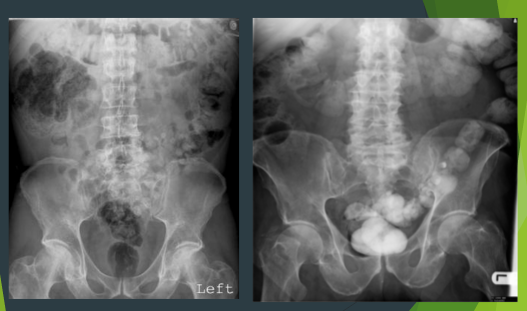

What is these xrays showing?

What symtpoms does he have from this pathology? 3

SMALL BOWEL OBSTRUCTION

TWO PATIENTS WITH

What are these two xrays showing?

What symptoms come with this pathology? 3

LARGE BOWEL OBSTRUCTION